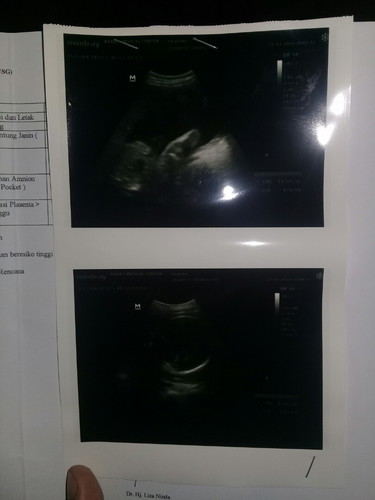

Hasil Nya

Ini 3d Dengan Harga 100Ribu Gmna Pndapat Bunda